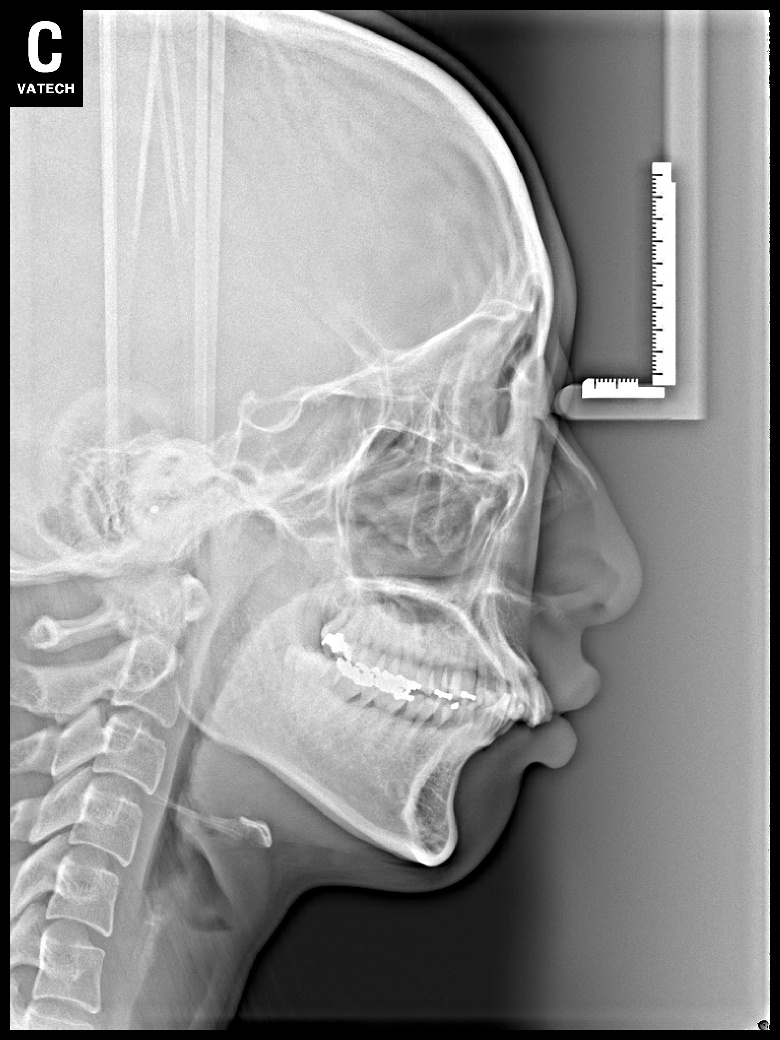

치료 후 사진입니다.